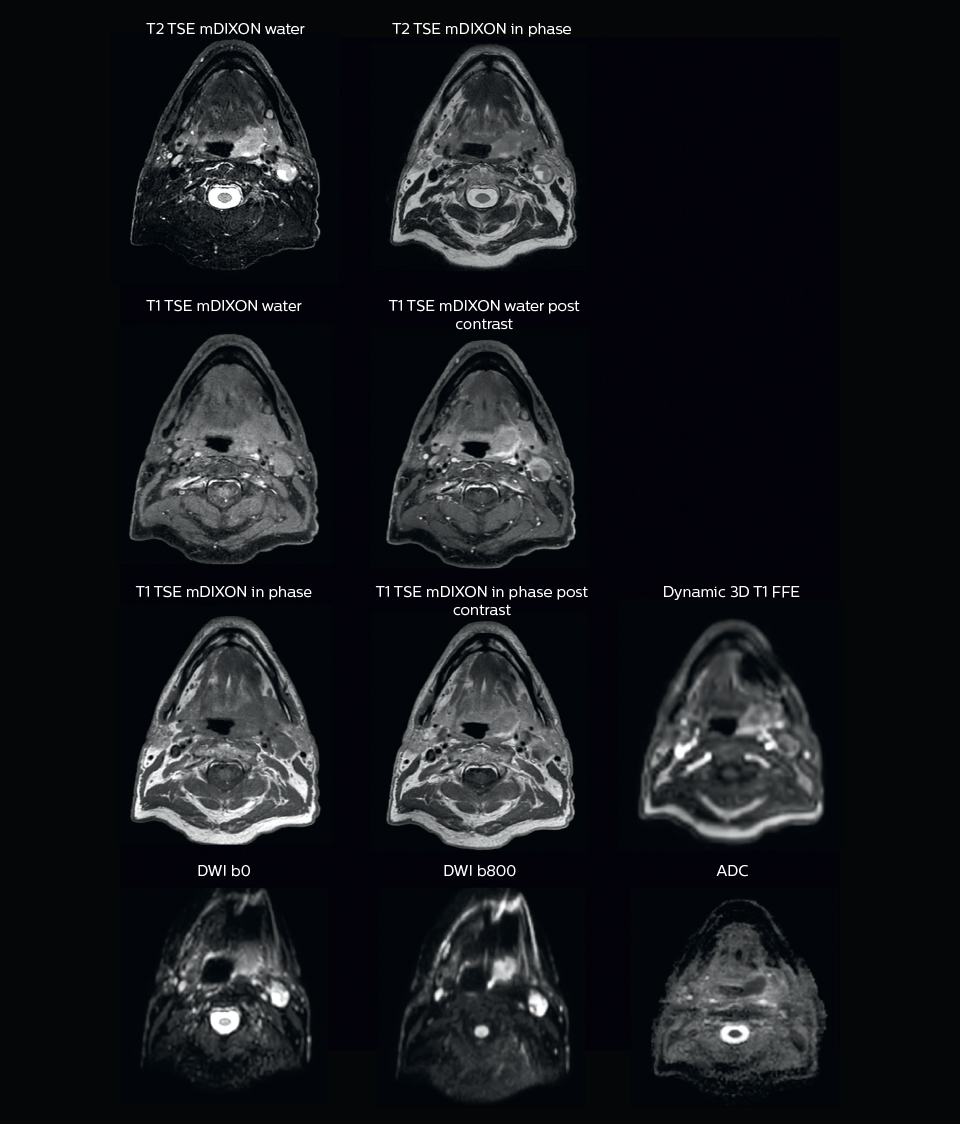

A 63-year-old patient with prostate cancer, cT3bNxM, Gleason 7, underwent MRI on Ingenia 3.0T MR-RT before radiation therapy.

Intraprostatic lesions are visible on the bTFE MR image, but not on the CT image. MRI shows excellent soft-tissue contrast for the visualization of critical structures like the rectum and penile bulb.

Fiducial markers (green arrows) are used in registration of MR images to CT, to transfer the MR-based delineations onto the CT image dataset.

“We use pre- and post-contrast T1- and T2-weighted sequences with the fast and robust mDIXON method for fat suppression,” says Dr. Philippens. “Dynamic contrast-enhanced imaging is performed with high temporal resolution and low spatial resolution, to see the contrast agent uptake in the tumor. Diffusion weighted imaging is used qualitatively to see how the tumor extends into another structure, rather than for strict delineation.”

“In postoperative patients who have had tumor growth along the cranial nerves, we use T2-weighted gradient echo (FFE) on our 3.0T MR-RT scanner to show the nerves for target delineation and look to see if there is still tumor left.”